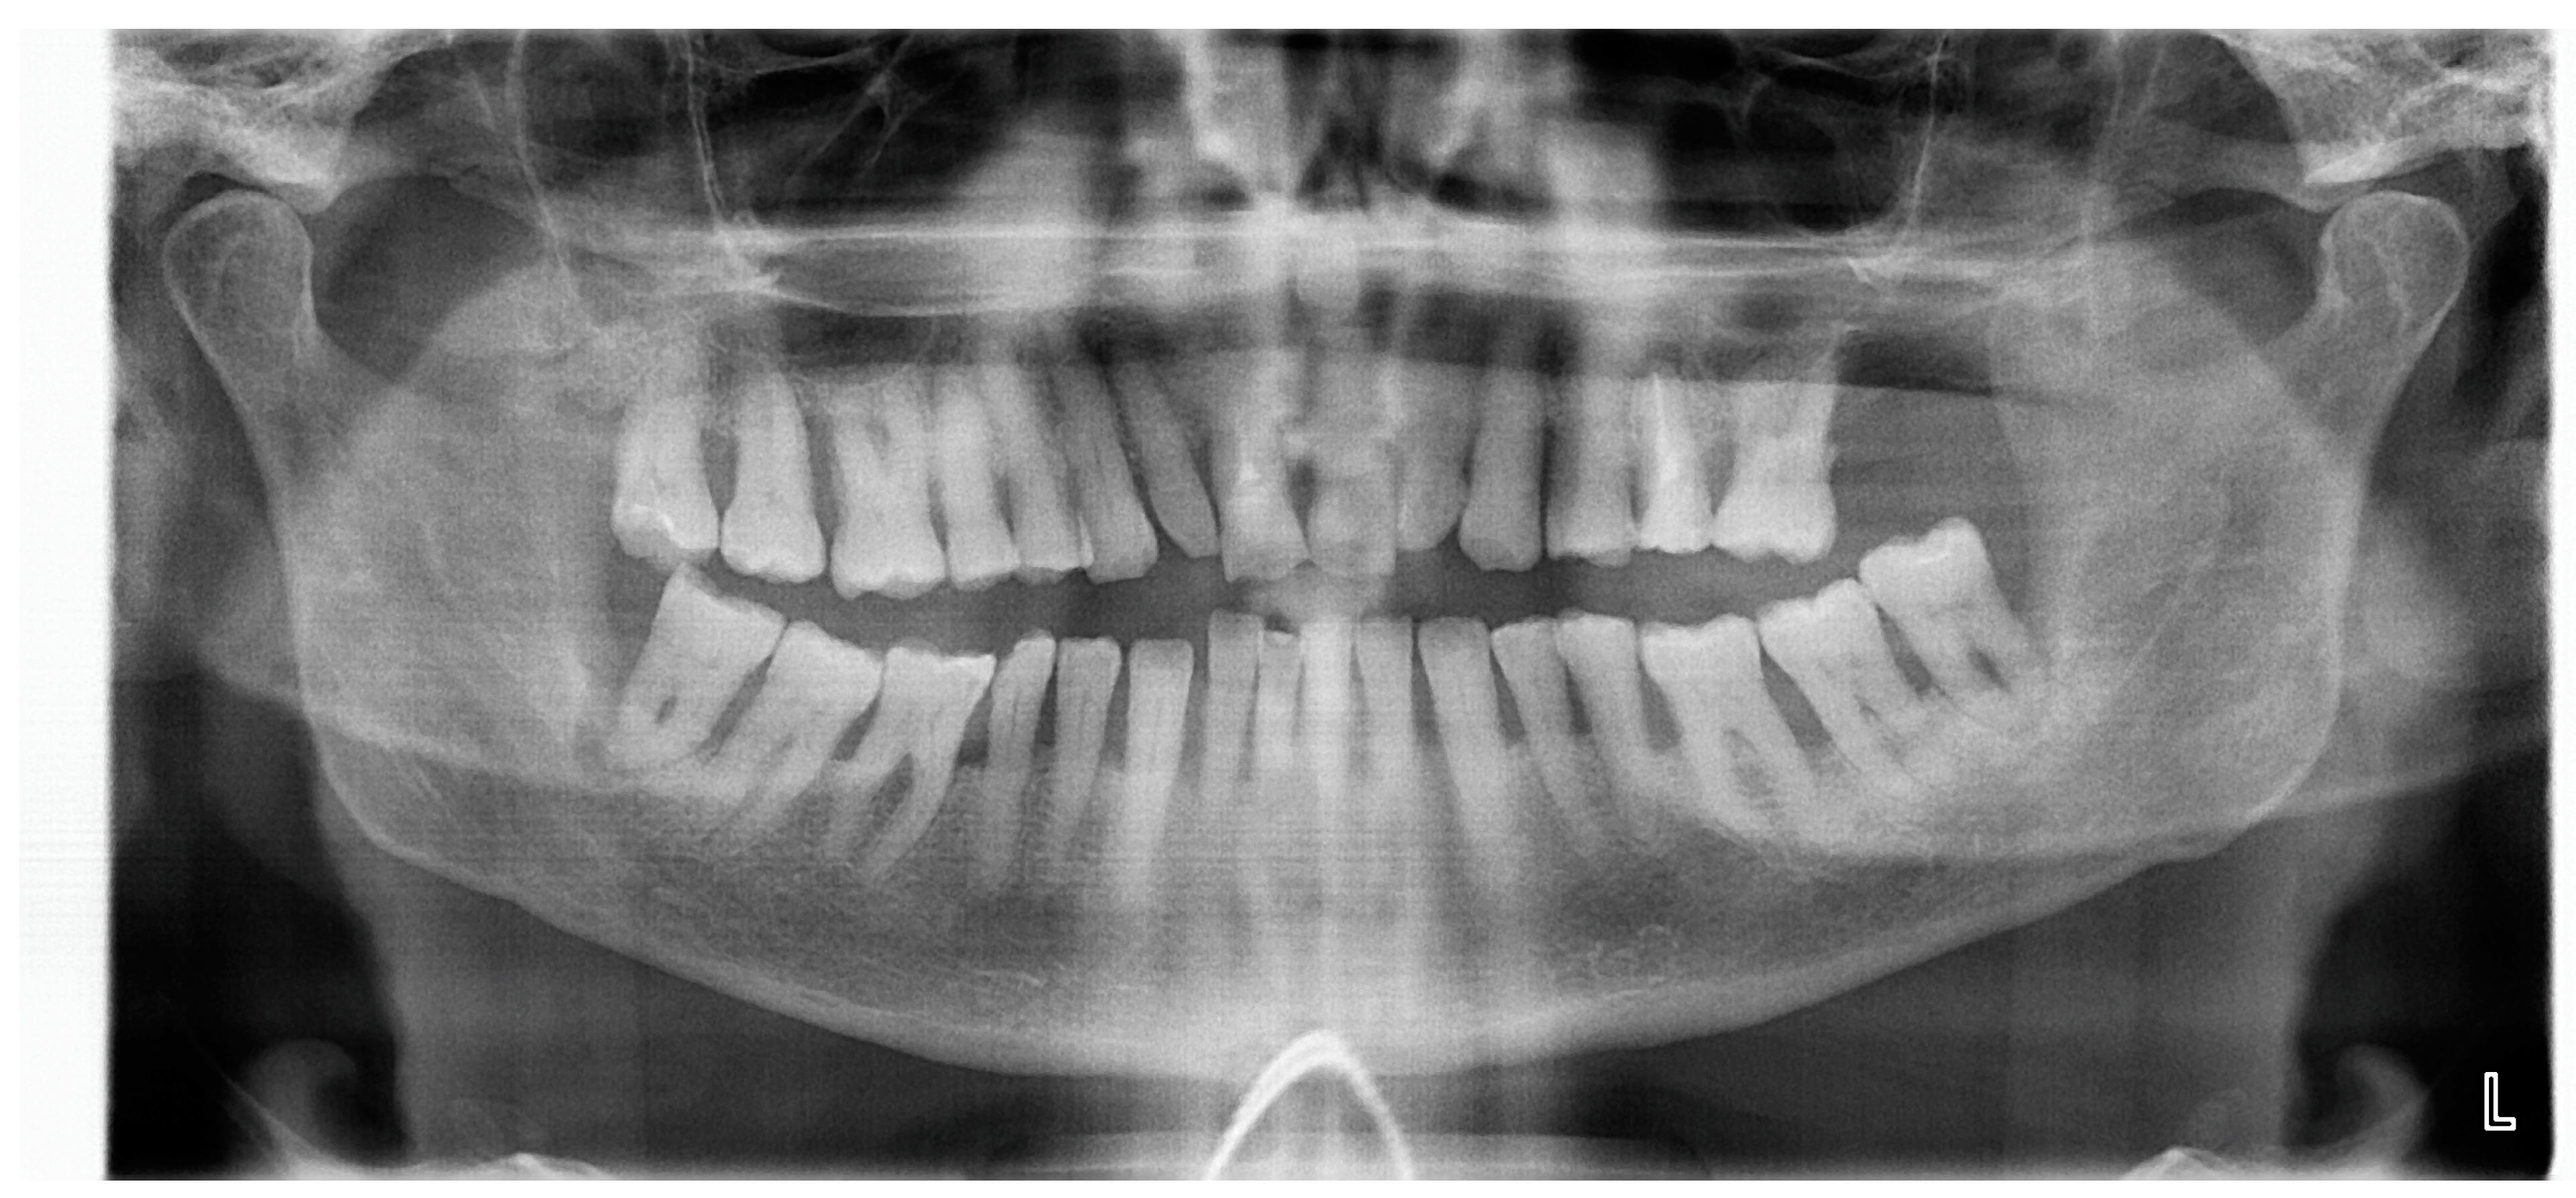

2. Material and Methods of Study